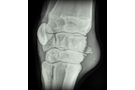

Artros karpalled häst

Vi gör alla typer av besiktningsröntgen (exportröntgen, hingströntgen, travarröntgen, hovbroskröntgen och unghäströntgen). Dessutom kan vi röntga halsar, ryggar, tänder, akuta frakturer m.m.